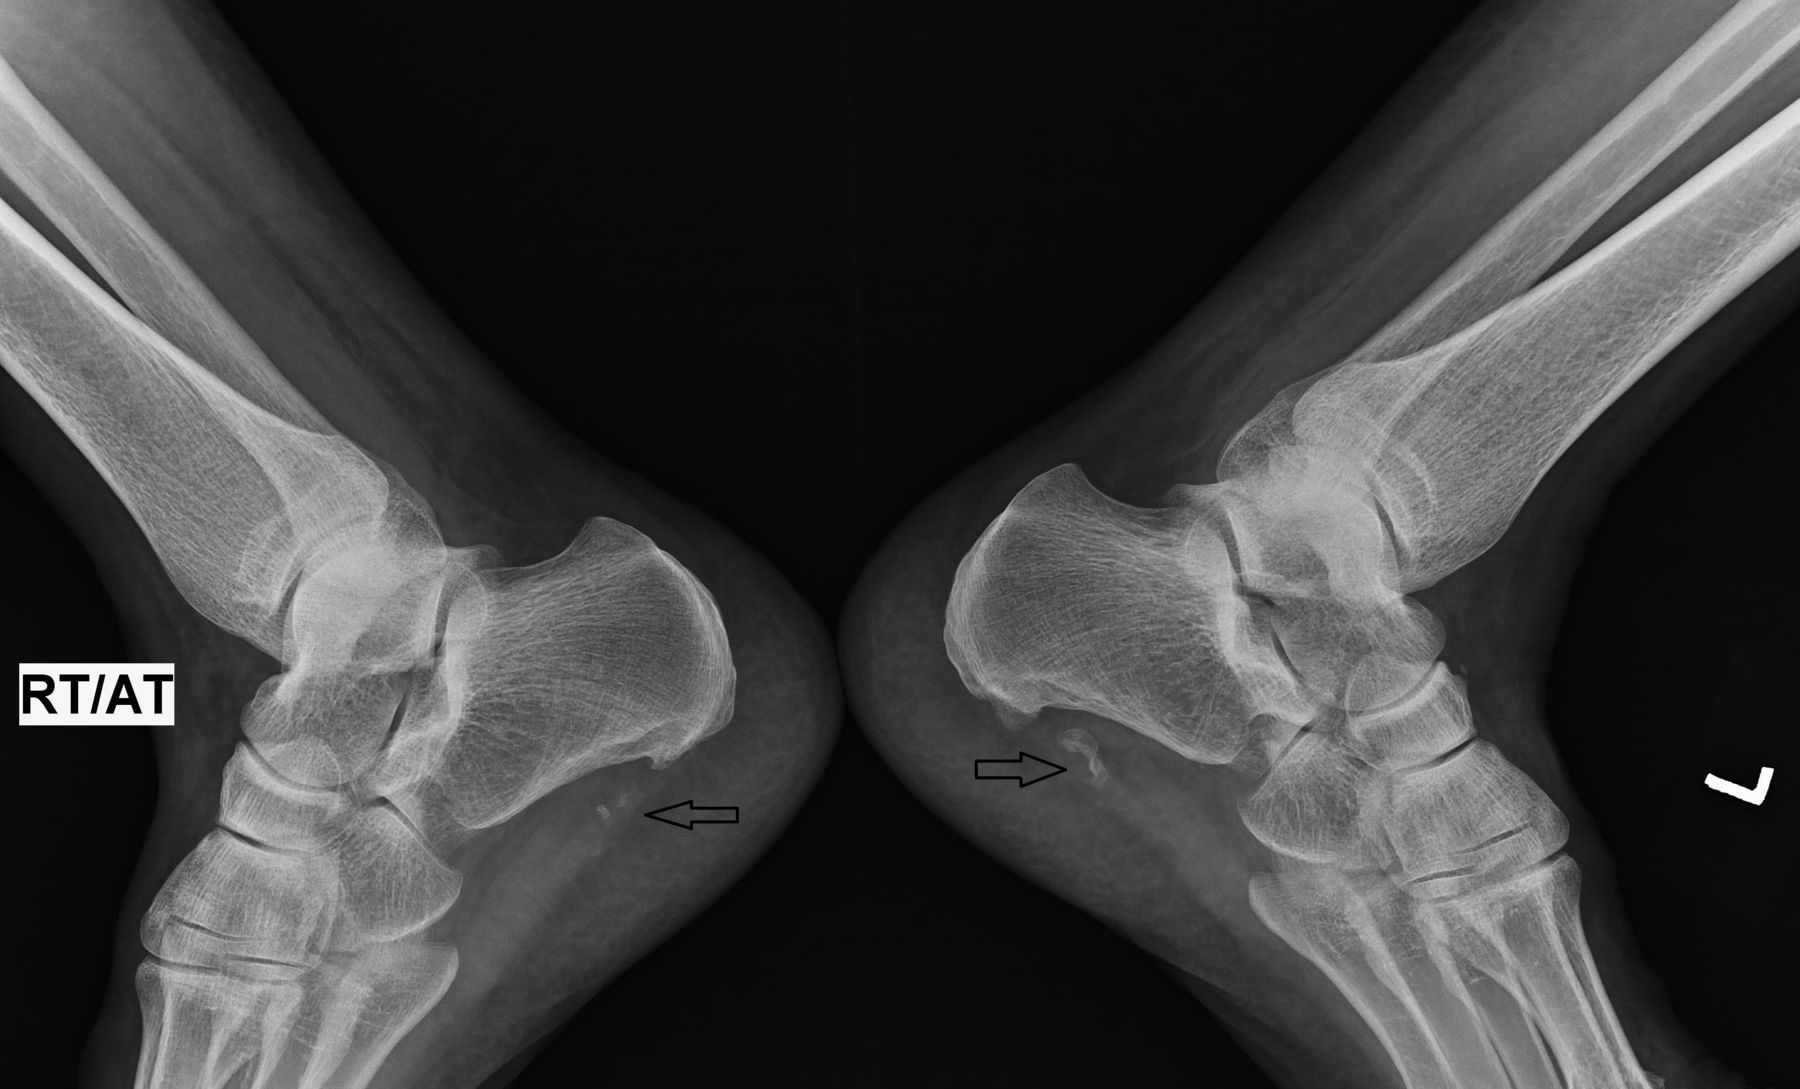

A spur on heel bone is essentially a calcium deposit that causes a bony protrusion on the underside of the heel bone. Over a period of several months, these calcium deposits build up, eventually forming a visible or palpable bony growth. These spurs are often identified through X-rays and are frequently associated with chronic inflammation in the soft tissue of the foot.

Many people have a spur on heel bone without even knowing it. They are often discovered incidentally when an X-ray is taken for another foot issue. However, when symptoms do occur, they can be quite painful and limiting. Common signs include: